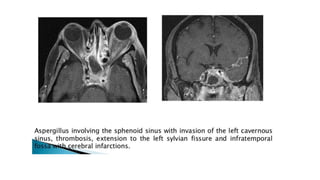

MRI

• Better for evaluating intracranial and intraorbital extension

• Evaluate for inflammatory change in orbital fat and extraocular muscles

• Obliteration of periantral fat is a subtle sign of extension

• Leptomeningeal enhancement progressing to cerebritis and abscess